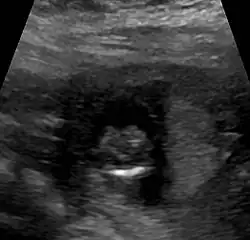

- alobäre Holoprosencephalie (keine Trennung, kein Interhemisphärenspalt, ein Hirnventrikel)[15]

Die Diagnose kann vorgeburtlich im Rahmen von Pränataldiagnostik durch insbesondere Feinultraschalluntersuchungen im zweiten Trimenon, teils aber auch schon früher, gestellt werden. Während die Feststellung der alobären und der semilobären Form oft recht einfach ist, ist die der lobären Holoprosencephalie komplizierter.

Nachgeburtlich sind die Schnittbildverfahren Sonographie und Magnetresonanztomographie Methoden der Wahl.[19]